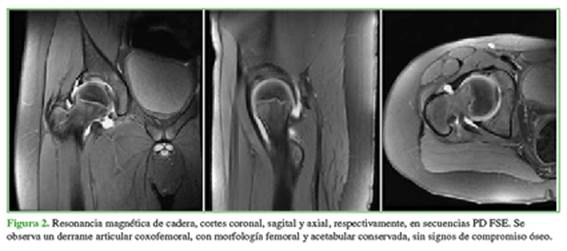

A las 48 h, el paciente fue examinado nuevamente en el consultorio externo. La madre negó que haya tenido fiebre, pero comentó que el niño estaba decaído y sin apetito. El dolor no se había incrementado, pero persistía, a pesar del tratamiento indicado. En el examen físico, el paciente continuaba con dolor a la movilización de la cadera derecha y limitación del rango de movilidad. Se solicitaron análisis bioquímicos, cuyos resultados fueron: recuento de glóbulos blancos 6.67 mill./mm³ sin desviación de la fórmula leucocitaria (60/1/1/29/9), proteína C reactiva 0,05 mg/dl; recuento de plaquetas 292 mil/mm³; APP 96,8% y KPTT 34.7’’ y un leve aumento de la eritrosedimentación con un valor de 40 mm. A los tres días, se realizó un nuevo control en el consultorio externo. Los síntomas habían mejorado, pero el día anterior, había tenido dos registros de temperatura de 37,5 °C. Se solicitaron nuevos análisis bioquímicos y una resonancia magnética de la cadera que reveló la presencia de un derrame articular coxofemoral, sin cambios morfológicos ni anormalidades de la intensidad de la señal de la médula ósea (Figura 2).